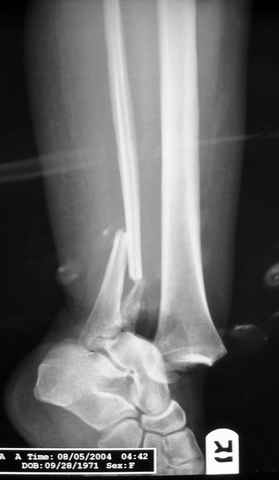

На прямой проекции послеоперационного Рг макроскопически все выглядит очень анатомично, при микроскопическом ( :-)) ) рассмотрении можно все-таки заметить вальгизацию тарана, суставная щель в латеральном отделе сустава несколько уже , чем в медиальном при отсутствии латерального смещения тарана. У меня был аналогичный случай (без LISS , без мини доступа) с вальгусным наклоном тарана при восстановленном ankle mortise при последовательном наблюдении с интервалами в 6-8 недель в послеоперационном периоде отмечалось прогрессирующее сужение суставной щели в латеральном отделе сустава, закончившееся посттравматическим ОА, к счастью боли умеренные, купируемые аналгетиками или своими эндорфинами:-))(активная пациентка, у которой нет времени на болезни....) Какова жизненная ситуация в приведенном вами случае? И последнее, что я хотел бы прояснить для себя - фиксация внутренней лодыжки: я обычно комбинирую фиксацию компрессирующим винтом со спицей - по идее ротационная стабильность должна быть лучше, чем один винт, каковы ваши наблюдения в этом плане?